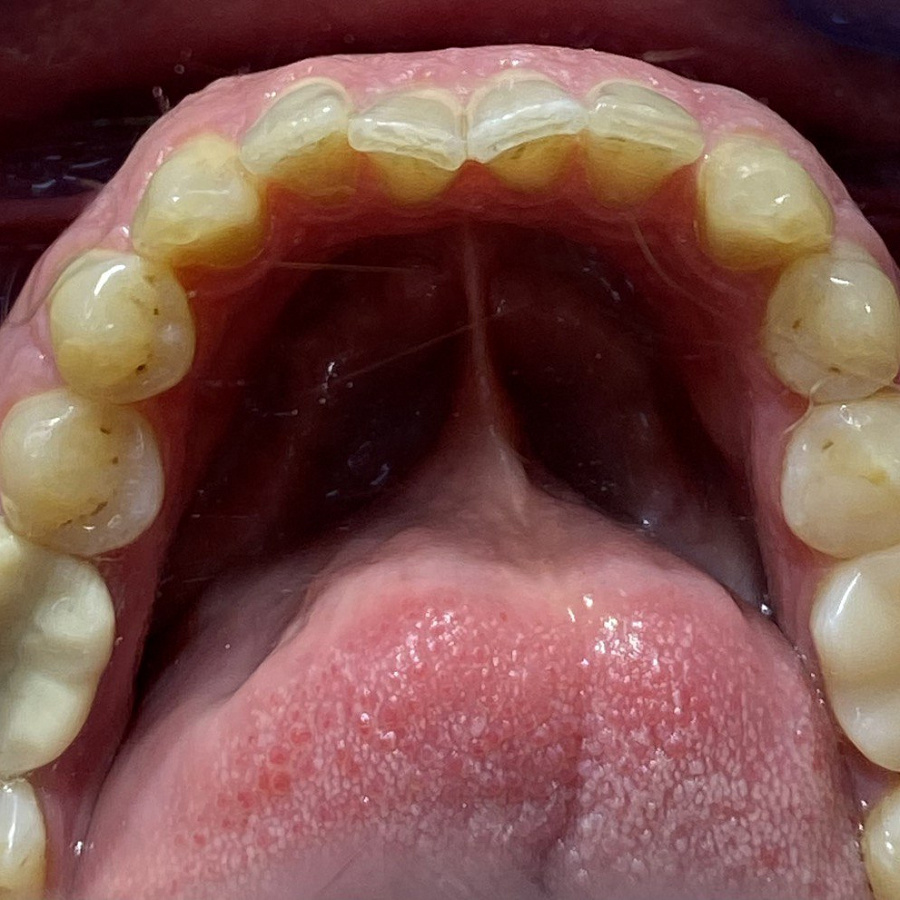

Пациент обратился с жалобами на неровные передние зубы верхней и нижней челюстей.

Диагностика показала:

• сужение зубных рядов,

• обратное перекрытие в области фронтальных зубов слева,

• разворот по оси передних зубов верхней и нижней челюстей,

• стираемость эмали зубов,

• индивидуальную микродентию 12 и 22 зубов.